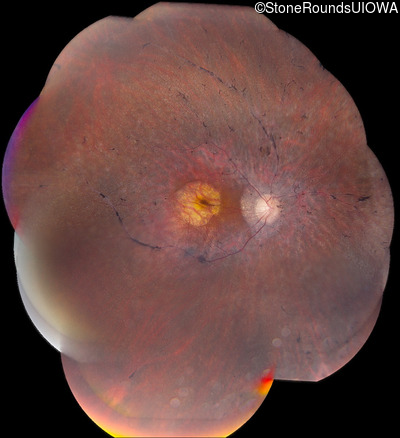

Age at visit: 63 years

OD OS

This 63 year old woman has had normal vision for most of her life, but recently developed difficulty seeing in dim light.

Diagnosis & molecular findings

AD Retinitis Pigmentosa SAG Cys147Phe TGT>TTT   AD